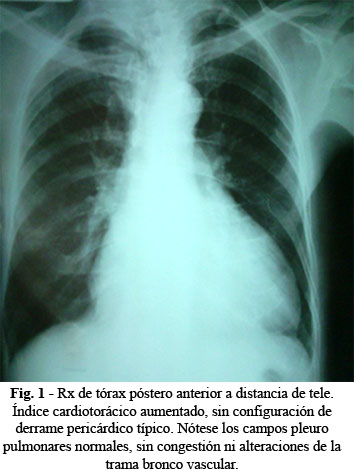

Exámenes complementarios: hemoglobina: 10 g/L. Eritrosedimentación: 138 mm/hora. Leucocitos: 3,5 x 109/L. Conteo de plaquetas: 100 x 109/L. Serología VDRL: Débil positivo o falso positivo. Células LE: Fueron positivas en 6 de las diez extracciones de sangre, en estudios realizados en diferentes ocasiones. Biopsia de piel: se aprecia hiperqueratosis con tapones crónicos, atrofia epidérmica, infiltrado linfocitario alrededor de anexos epidérmicos, incontinencias pigmentarias. Compatible con LES. Filtrado glomerular: normal. Creatinina: normal (89 mmol/L). Glicemia: 5,6 mmol/L. Transaminasa glutámico pirúvica: 24 mmol/L. Amilasa Pancreática: normal. Rx de tórax (distancia de tele): índice cardiotorácico aumentado, pero sin configuración de derrame pericárdico típico (Fig. 1).